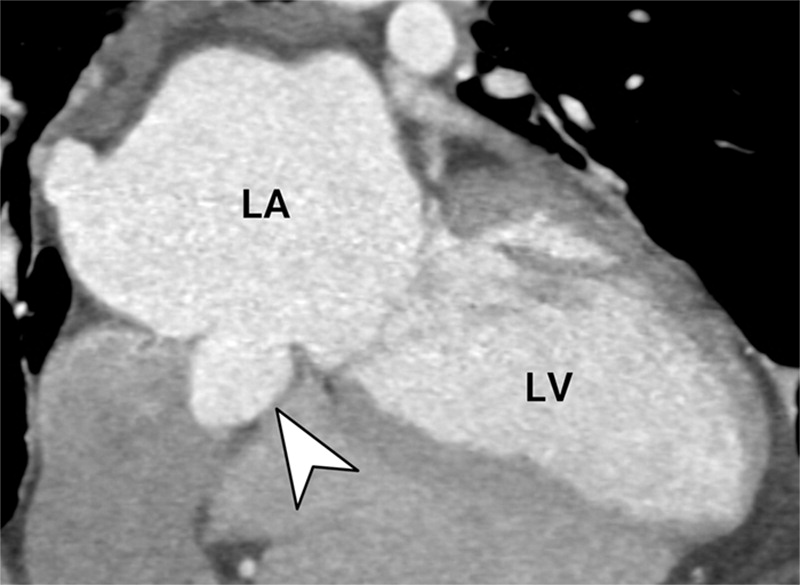

A systematic approach to cardiac pouchings and outpouchings can help radiologists maximize diagnostic accuracy and guide patient management or further workup. bit.ly/42HCBY3 UCLA Radiology Radiology of USC

A systematic approach to cardiac pouchings and outpouchings can help radiologists maximize diagnostic accuracy and guide patient management or further workup. bit.ly/42HCBY3 <a href="/RadiologyUcla/">UCLA Radiology</a> <a href="/RadiologyUSC/">Radiology of USC</a>